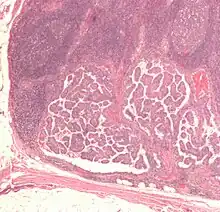

Micrograph of a papillary thyroid carcinoma demonstrating diagnostic features (nuclear clearing and overlapping nuclei).